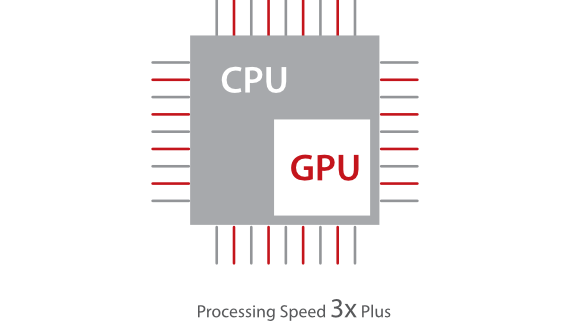

Based on the deep insights of customer needs, the DC-60 ECHO with X-Insight is designed to deliver high efficiency with precision imaging, which is empowered by eXpress Clarity, eXceptional Intelligence and eXceeding Experience.

Experience with high productivity